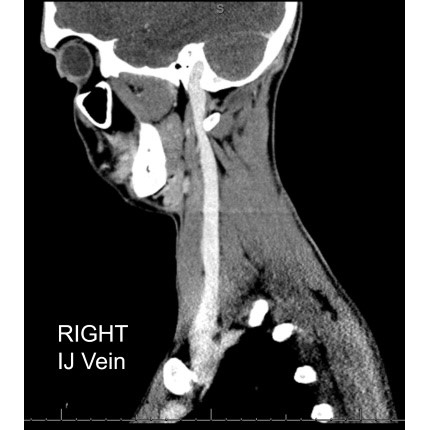

| A Pain In The Neck - Page #3 | |||